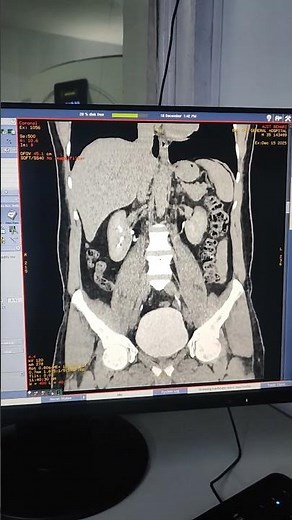

Image Generator - Urogram

Image Generator - Urogram CT

Urogram MIPS - CT

Urogram - 3D